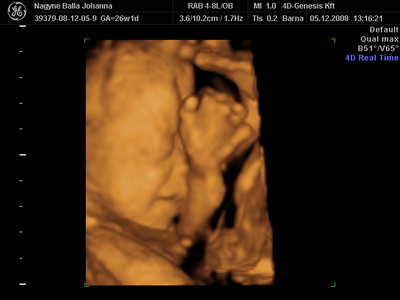

Lukács mindenkinek köszöni a dicséreteket! Én is.

Kicsibé! Köszike! Bár én most inkább azt mondom, tiszta apja. De olyan mindegy ugye? Csak egészséges legyen, meg végre van.